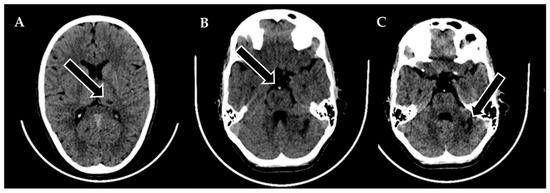

A 9-year-old male was admitted to a regional hospital due to a persistent complaint of diarrhea, exceeding ten episodes in two days, accompanied by a single episode of vomiting, tension headache, and mild vertigo. Initial diagnostic assessments did not reveal any notable abnormalities, leading to a diagnosis of gastroenteritis. Following rehydration therapy, the patient’s overall condition improved, and discharge plans were being considered. However, on the subsequent day after admission, at approximately 6 pm, the patient suddenly experienced weakness localized to the left side of his body. Recognizing the urgency of the situation, an emergency consultation with a neurologist was promptly arranged. Two hours following the onset of these new symptoms, a computed tomography (CT) scan of the brain was conducted (Figure 1), which did not show any acute changes in the brain. Nevertheless, the CT scan did reveal two hypodense regions in the left cerebellum, which raised suspicion of malignancy, along with a hyperdense appearance of the basilar artery (BA). Additionally, a hypodense region was noted in the left thalamic region, suggesting a potential prior lacunar stroke.

Figure 1. Emergency CT scan of the brain. (A) Hypodense region in the left thalamic region; (B) hyperdense basilar artery (HDBA) sign; (C) 2 hypodense regions in the left cerebellum.